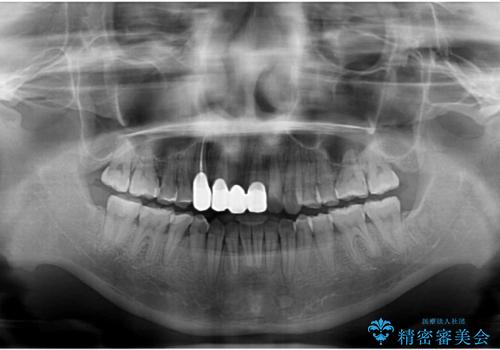

- 転倒により前歯の一部が欠けてしまったとのことで来院された患者様です。

神経が保存できる歯、神経を除去しなければならない歯、抜歯が必要な歯があり、ブリッジやインプラントなどによる治療を提案しました。

元々歯並びが気になっていたとのことで、前歯の治療を行うことを契機に矯正治療も行うこととしました。

本来であれば積極的に小臼歯を抜歯して口元を下げても良いのですが、前歯を1本抜歯しないといけなくなったため、非抜歯矯正をインビザラインを用いて行うこととしました。